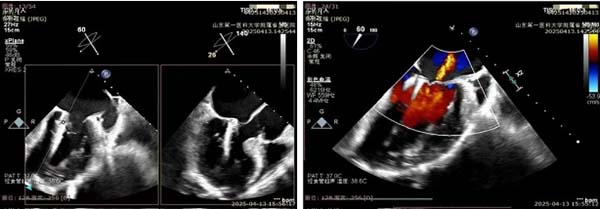

手术当天,杨麟、曹国威团队严密监测循环与呼吸参数,确保麻醉平稳。朱梅实时解读瓣膜解剖与反流评估,为操作提供精确导航。术中,在王安彪指导下,谭琦先经左胸小切口建立心尖通路,送入二尖瓣夹合器,通过TEE引导,精准定位于后叶反流最重区域,首次夹合即见强回声信号,瓣叶开放良好且无狭窄,仅存轻度残余反流,于是,在高难度操作下再次植入第二枚夹合器,完全消除了受累区的反流信号。经过短暂观察后,如术前手术团队所预期,在解决患者二尖瓣反流的问题后,患者左心室负担加重,主动脉瓣反流量增加至重度。

夹子精准定位捕获,二尖瓣返流明显改善

主动脉瓣返流明显增加